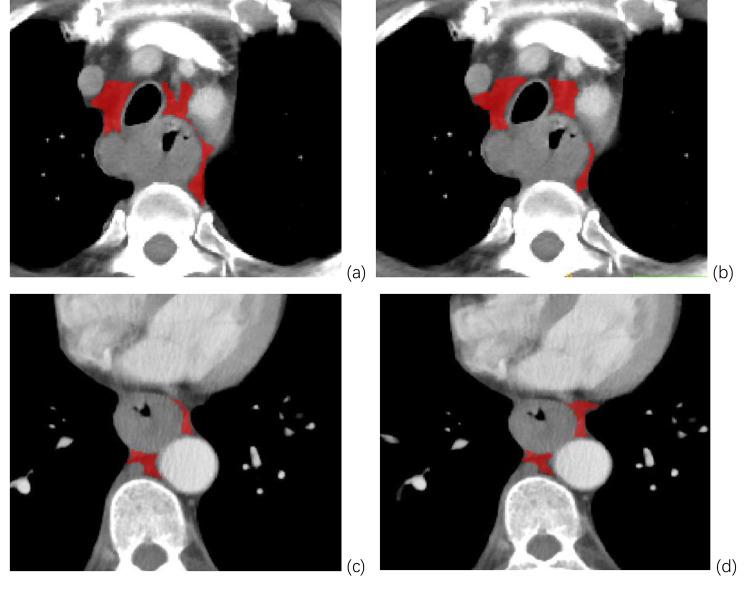

METHODS

A total of 166 patients with locally advanced ESCC in two medical centers were retrospectively analyzed. The volume of interest (VOI) of meso-esophageal fat and tumor were manually delineated on enhanced chest CT using ITK-SNAP. Radiomics features were extracted from the VOIs by Pyradiomics and then selected using the t-test, the Cox regression analysis, and the least absolute shrinkage and selection operator. The radiomics scores of meso-esophageal fat and tumors for OS were constructed by a linear combination of the selected radiomic features. The performance of both models was evaluated and compared by the C-index. Time-dependent receiver operating characteristic (ROC) analysis was employed to analyze the prognostic value of the meso-esophageal fat-based model. A combined model for risk evaluation was constructed based on multivariate analysis.

回顾性分析两个医疗中心的 166 例局部晚期 ESCC 患者。采用 ITK-SNAP 手动勾画增强胸部 CT 中食管中段脂肪和肿瘤的感兴趣区(VOI)。采用 Pyradiomics 从 VOI 中提取放射组学特征,然后通过 t 检验、Cox 回归分析和最小绝对收缩和选择算子选择特征。通过线性组合选定的放射组学特征构建食管中段脂肪和肿瘤的放射组学评分,用于 OS 分析。通过 C 指数评估和比较两种模型的性能。采用时间依赖性接收器工作特征(ROC)分析评估基于食管中段脂肪模型的预后价值。基于多变量分析构建了风险评估的联合模型。